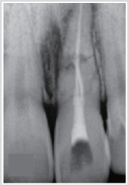

▲従来のレントゲンでは欠損部が

わかりづらいです。